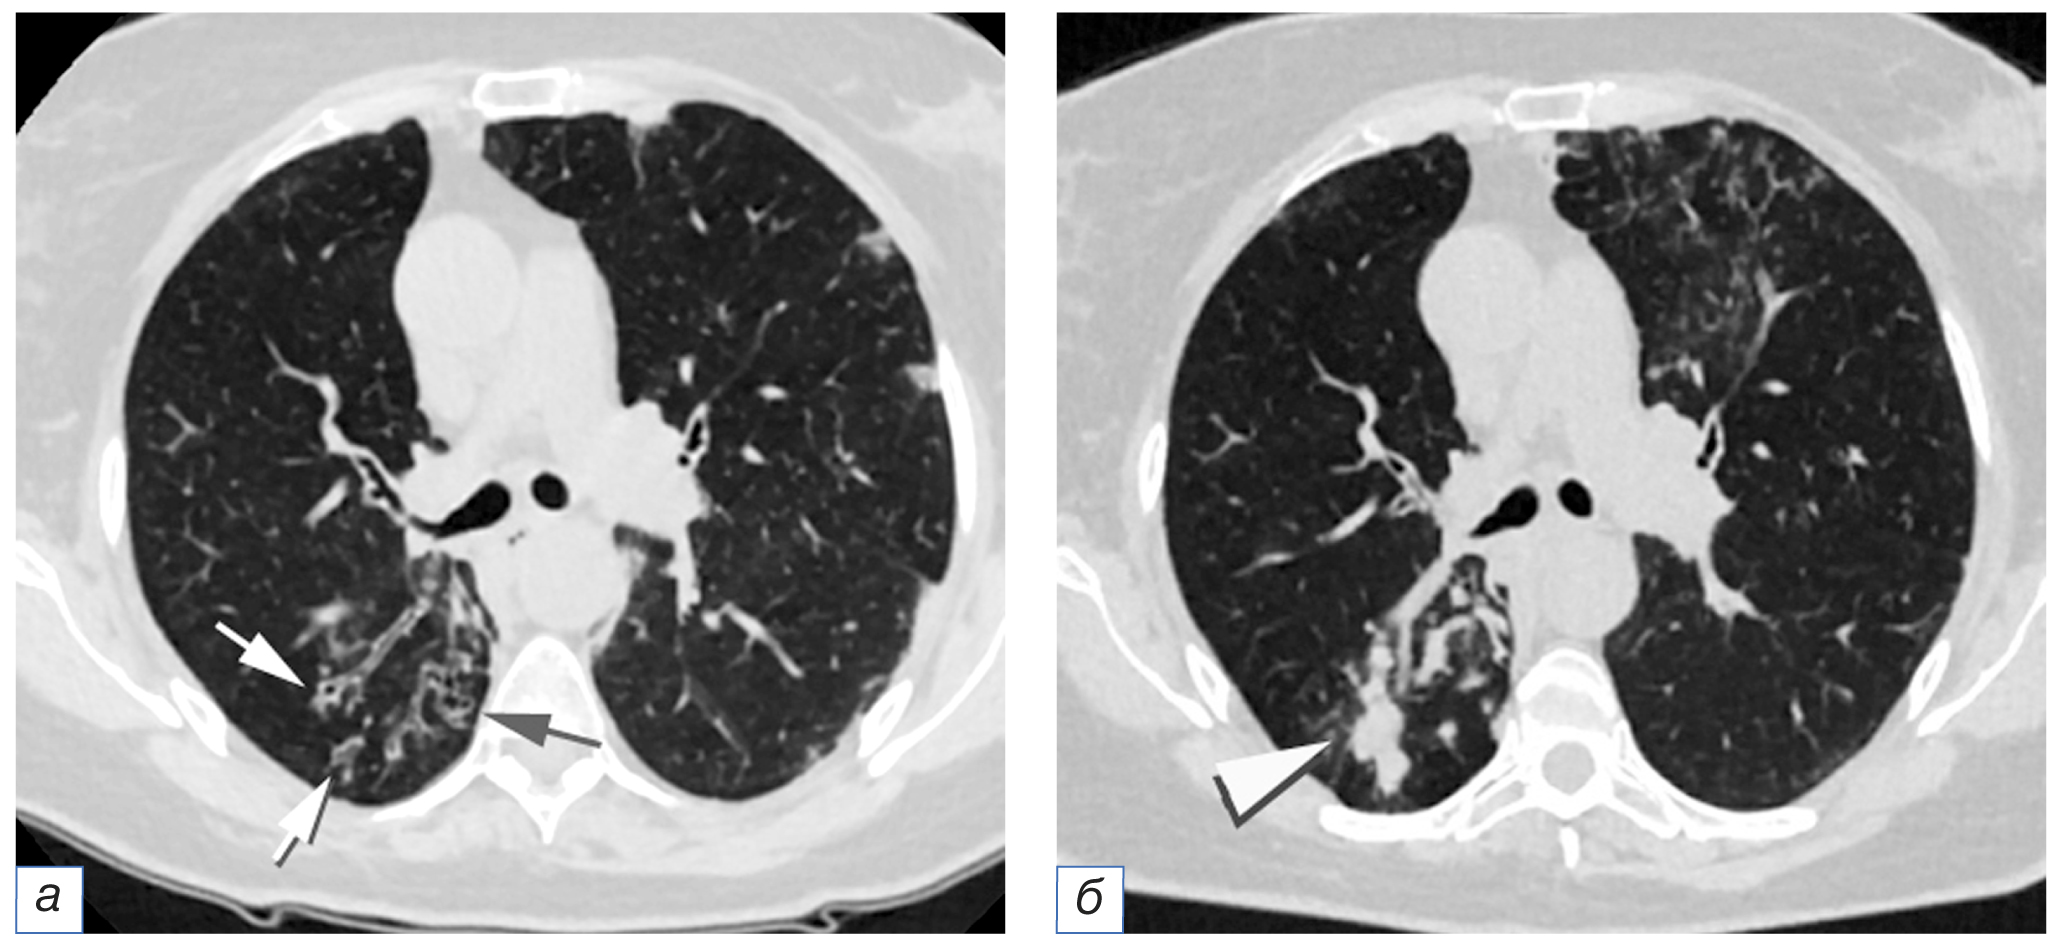

- бронхоинвазивный аспергиллёз: бронхи трансформируются в бронхо- и бронхиолоэктазы, или имеющиеся бронхоэктазы увеличиваются в размерах, изменяют форму (кистовидные или мешотчатые бронхоэктазы), заполняются слизью и мицелием гриба; в дальнейшем развивается воспалительная инфильтрация окружающей паренхимы лёгкого (рис. 5).

Рис. 5. Пациент C., 50 лет, с аспергиллёзом лёгких, возникшем на фоне COVID-19 (COVID-АЛ): а — бронхо- и бронхиолоэктазы в нижней доле правого лёгкого (стрелки); б (через 19 дней) — формирование бронхиолоэктазов в верхней доле левого лёгкого, увеличение размеров и заполнение мицелием гриба бронхоэктазов нижней доли правого лёгкого (треугольная стрелка).

Fig. 5. Patient C., 50 years old, CAPA: а — bronchiectasis and bronchiolectasis in the lower lobe of the right lung (arrows); б — 19 days after, the formation of bronchiolectasis in the upper lobe of the left lung, an increase in size and filling with mycelium of the fungal bronchiectasis of the lower lobe of the right lung (triangular arrow).